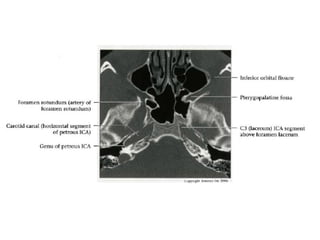

Petrous (C2) segment

• Contained within carotid canal of temporal bone

- Surrounded by extensive sympathetic plexus

- Two C2 subsegments joined at genu

• Short vertical segment - anterior to internal jugular vein

(lJV)

• "Genu" (where petrous ICA turns anteromedially in front

of cochlea)

• Longer horizontal segment

- Exits carotid canal at petrous apex